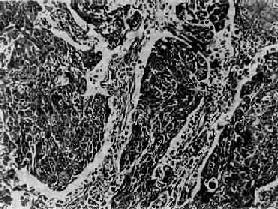

(2)小细胞:发生率在肺中居第二位(临床统计在40%以上,尸检统计占15%~25%)。患者男多于女(20:1),发病年龄约在35~60岁。小细胞肺亦多发生于肺中央部,生长迅速,转移较早,恶生度高,5年存活率仅1%~2%。小细胞细胞很小,呈短梭形或淋巴细胞样,有些细胞呈梭形或多角型,胞浆甚少,形似裸核。细胞常密集成群,由结缔组织加工分隔(图9-33)。有时细胞围绕小血管排列成假菊形团或管状结构。小细胞肺起源于支气管粘膜和粘液腺内Kultschitzky细胞,是一种具有异源性内分泌功能的肿

小细胞肺<a href=癌"/>

图9-33 小细胞肺

短梭形细胞平行排列,群集成团(燕麦细胞型)